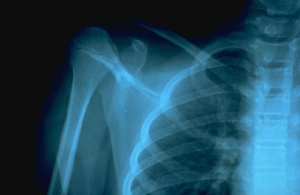

Radiografía de hombro

La implementación de tratamiento médico despues de una fractura es vital, en el pronóstico del paciente con osteoporosis.